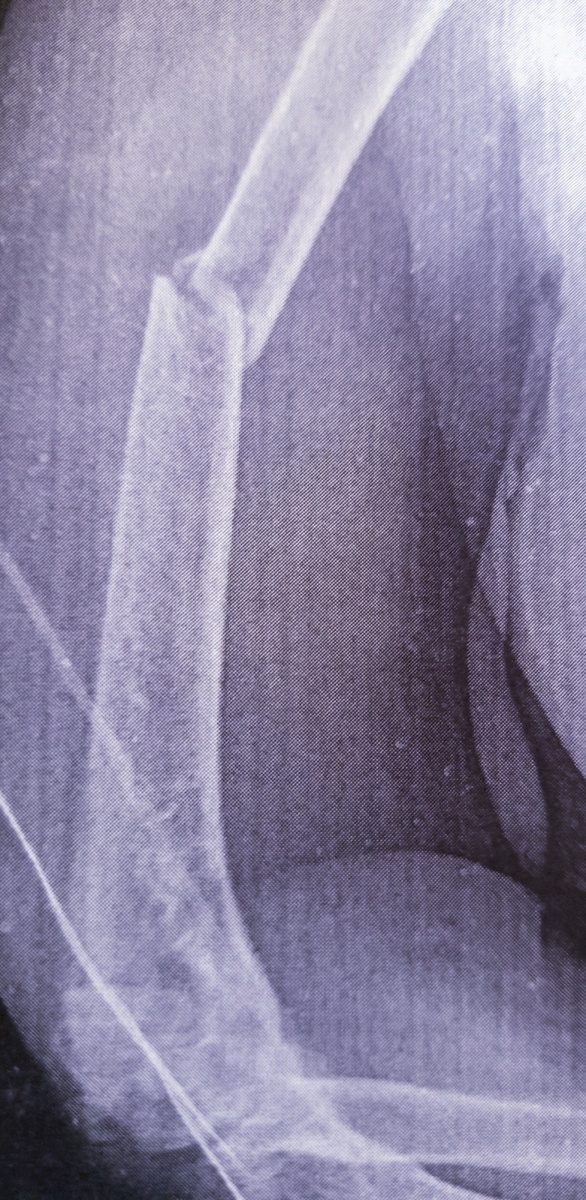

Пациент едва поместился на кассету, очень крупный, но в сознании. Упал с небольшой высоты, с лесов, но не обычным образом , а на пятую точку приземлился, так как сидя падал.Перелом тазобедренного.

Мы ушли , а минут через тридцать снова позвали на контрольный снимок.

—Так сейчас же только один сустав тогда снять?-уточнила я у травматолога, увидев, что вытяжку сделали только на одной ноге.

–Да , конечно,-согласился он.

Тут уже проще было и подложить кассету и вынуть. Пациента жалко очень, он не сдерживал слез.